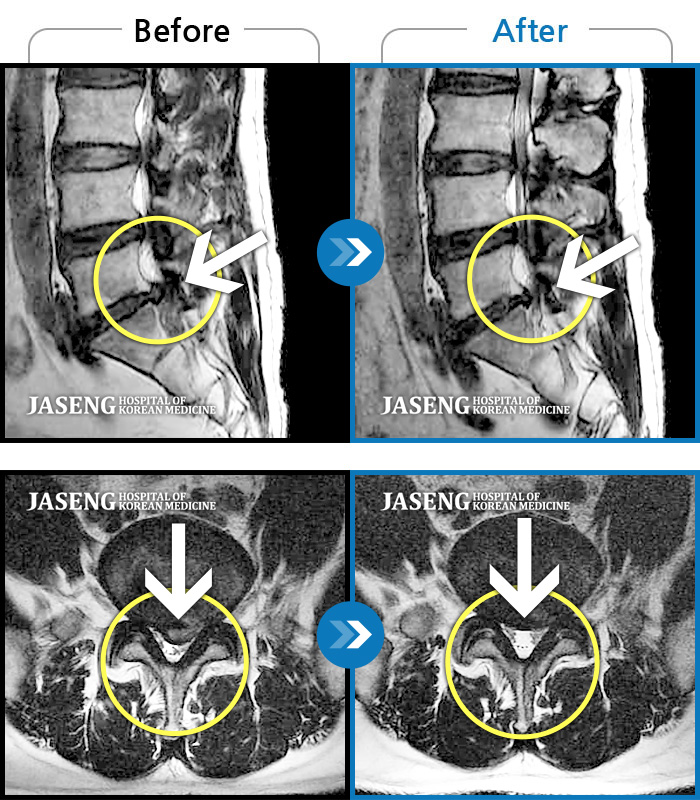

허리디스크

잠실 · 한상욱 원장

허리, 우측 엉치와 다리 후면 및 발끝까지 저림과 통증이 심하고 힘까지 빠진다.

촬영시기

2022.06.15 ~ 2022.11.11

2022.12.02